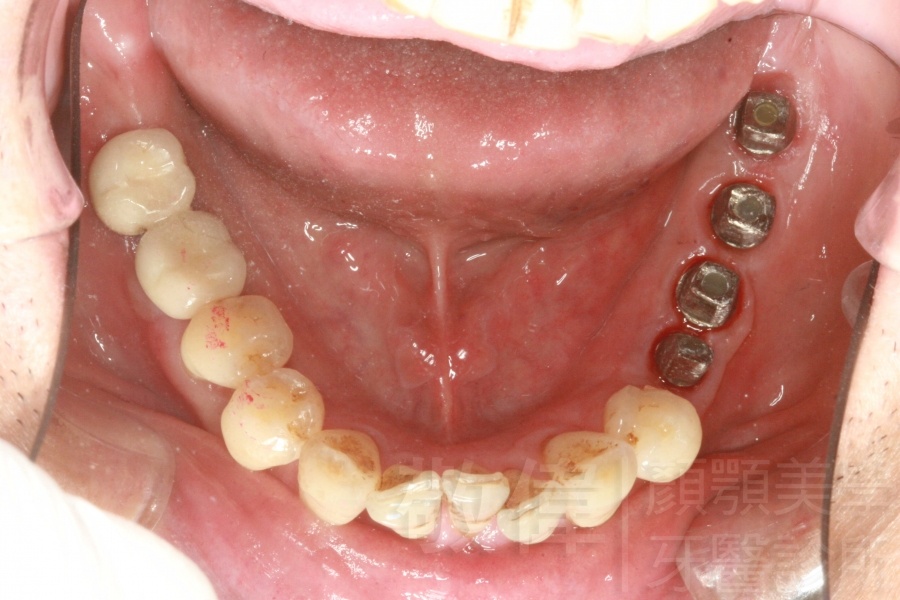

人工植牙/左下後牙區植牙

左下後牙區植牙後的支台柱   植牙後